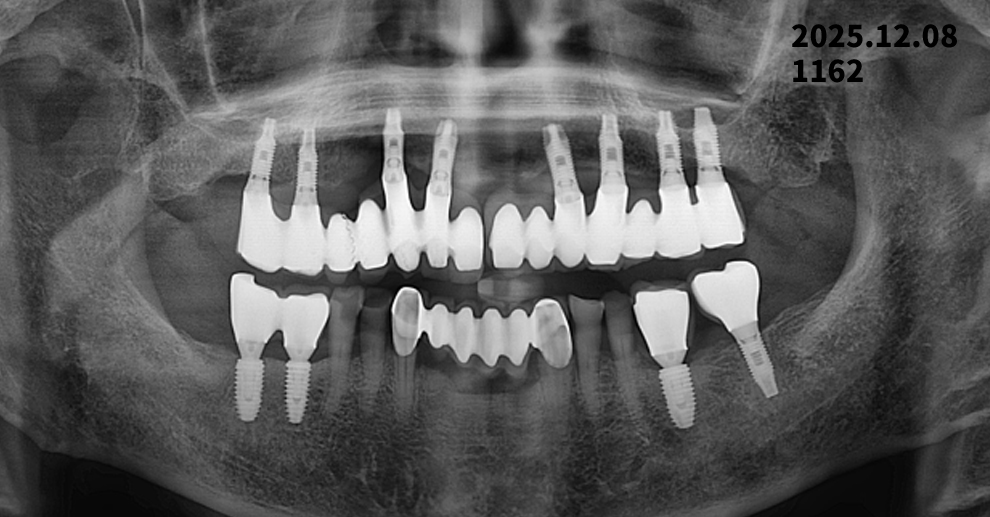

임플란트 14년 경과 후 치조골 변화

2011년 식립 → 2025년 정기검진 X-ray 비교 | 광진구치과

2011년 임플란트 식립 후 약 14년이 지난 2025년 정기검진 파노라마 X-ray를 통해

임플란트 주위 치조골 변화를 추적 관찰한 사례를 소개해 드리겠습니다.

검사 개요

- 2011년 : 임플란트 식립 후 파노라마 X-ray 촬영

- 2025년 : 정기검진 파노라마 X-ray 촬영

- 비교 항목

- 임플란트 주위 치조골 높이 변화

- 골 소실 여부

- 장기 안정성 평가

상악(윗턱) 임플란트 변화

2011년과 2025년 파노라마 X-ray를 비교해 보면,

- 임플란트 나사산 주변의 골 접촉 상태가 전반적으로 잘 유지

- 임플란트 목 부위에서 관찰되는 경미한 골 흡수는

장기 사용 임플란트에서 흔히 나타나는 생리적 변화 범위

여러 개의 임플란트가 보철물로 연결된 구조로

저작력이 비교적 고르게 분산되어 안정적인 상태로 판단됩니다.

하악(아랫턱) 임플란트 변화

하악 후방 임플란트 부위에서도

- 2011년 대비 뚜렷한 치조골 감소 소견 없음

- 임플란트 주위에 염증을 의심할 만한

방사선 투과성(검게 보이는 부위) 소견은 관찰되지 않음

👉 현재 영상 기준으로는

임플란트 주위염을 강하게 의심할 소견은 없는 상태입니다.

14년 경과 임플란트, 종합 평가

✔ 임플란트 식립 후 10년 이상 경과한 사례

✔ 급격한 골 소실이나 임플란트 실패 소견 없음

✔ 정기검진과 관리가 잘 이루어진 예후가 좋은 케이스